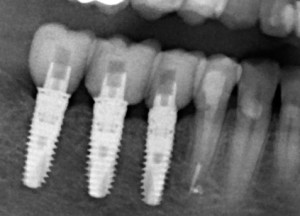

Почему всё это должен знать имплантолог? Дело в том, что суммарная длина конструкции «имплантат-абатмент-коронка» должна оставаться неизменной, если мы хотим, чтобы коронка была в прикусе и нормально функционировала. Это значит, что небольшая длина импланта должна быть компенсирована раздутым эго и большим джипом увеличением размеров супраструктуры, а именно — абатмента и коронки:

Но это еще не самое веселое. Допустим, мы решили проблему соединения «имплант-абатмент», у нас нет проблем с люфтами, а сам имплантат настолько хорошо интегрировался, что способен любую нагрузку в любом направлении. Возникает другая проблема — размер супраструктуры и соответствие ее нормальной биологической длине коронки зуба:

На фотографии выше, коронки опираются на обычные импланты, но даже в этом случае увеличение высоты супраструктуры усложняет гигиену и требует более пристального дальнейшего наблюдения. С ультракороткими имплантами, если честно, всё еще хуже.

Как будет выглядеть такая конструкция? Какой длины будут коронки? Возможно, на эстетику даже можно забить, ведь для некоторых людей красота зубов в боковом сегменте челюсти за пределами эстетически значимой зоны не так важна, но… как быть с уходом за протетической конструкцией и ежедневной гигиеной? Ведь, чем больше по размеру протез, тем сложнее за ним ухаживать. Тем больше мест, где может остаться зубной налет, а это, как вы понимаете, может привести к очень неприятным последствиям — периимплантиту, что для ультракоротких имплантов очень критично. А застревание пищи между протезом и десной? Можно ли назвать это «повышением качества жизни пациента»? Вряд ли.